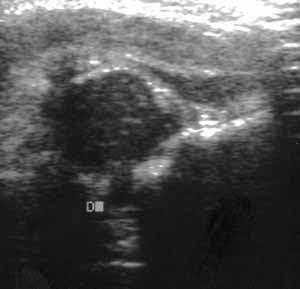

Ультразвуковая диагностика дисплазии тазобедренных суставов.

Рис. 6. Несформированный сустав.